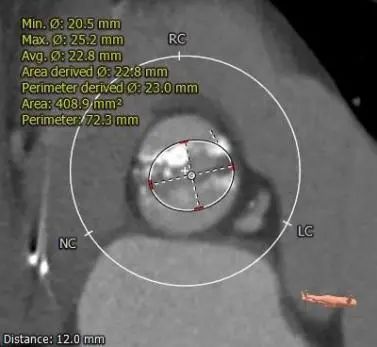

主动脉根部测量

瓣上测量

1.Type 0 型二叶瓣,瓣叶增厚,双侧瓣叶边缘连续条状钙化,瓣膜锚定难度适中,瓣膜植入受两侧钙化挤压存在移位风险及瓣周漏风险。

3.推荐22mm球囊预扩,根据球扩后腰征决定AV26还是AV29瓣膜,瓣环下2mm定位释放,建议释放后调整至右前斜足位 RAO 6 CRA 35 左右进一步确定人工瓣膜展开形态。